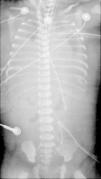

The baby was born in September 2010. She was immediately intubated after birth, the Apgar score (1st and 5th minutes) was 3/6, and she was started on mechanical ventilation (SIPPV; frequency=60min−1; inspiratory pressure=25cmH2O; FiO2=1.0). The initial arterial blood gas sample after admission to the neonatal intensive care unit (NICU) reported abnormal values: pH=6.8, PaO2=43mmHg, PaCO2=99mmHg, HCO3=16; BE=−26; lactate=6mmol/L. She was changed to high frequency oscillatory ventilation (HFOV) and started inhaled nitric oxide (20ppm). The echocardiogram 2D revealed a normally structured heart and severe pulmonary hypertension. The baby presented systemic arterial hypotension and inotropic and vasopressor support was started with dopamine+dobutamine. The oxygenation index was 44 and venoarterial ECMO (VA-ECMO) was started at hour five of life, with normalization of pH and blood gases. She underwent surgical correction of the left diaphragmatic defect with prosthesis, on day two of life. The chest X-ray never showed air filled lungs (Fig. 1). The baby was kept on VA-ECMO for 16 days, when the team decided to stop treatment, after several failed trials to wean from ECMO. The baby died and the autopsy revealed not a left but a bilateral diaphragmatic defect and confirmed very small volume with histological characteristics of hypoplastic lungs.